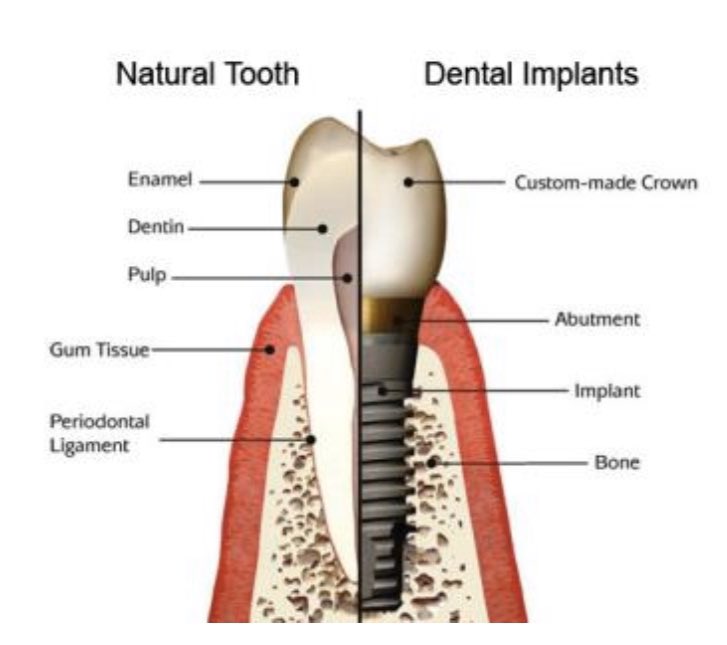

🦷 الفرق بين الزرعة والسن الطبيعي:

الطبيعي محاط بأربطة التي تعطي المريض الاحساس بقوة العضة والإطباق في الزراعه اقل

الطبيعي مرن بسبب وجود الاربطة حوله بينما الزرعة ملتحمة بالعظم لاتتحرك بالتقويم

يكون عمر السن الطبيعي أطول من عمر الزرعة.

الطبيعي محاط بأربطة التي تعطي المريض الاحساس بقوة العضة والإطباق في الزراعه اقل

الطبيعي مرن بسبب وجود الاربطة حوله بينما الزرعة ملتحمة بالعظم لاتتحرك بالتقويم

يكون عمر السن الطبيعي أطول من عمر الزرعة.